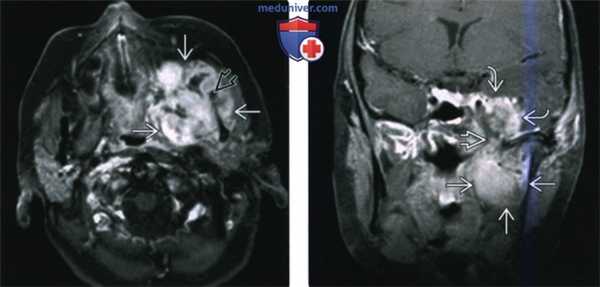

(Слева) На аксиальной КТ с КУ в жевательном пространстве справа визуализируется злокачественная фиброзная гистиоцитома нижней челюсти в виде минимально контрастирующегося солидного объемного образования, разрушающего ветвь и тело нижней челюсти. Жевательное пространство является известным местом возникновения сарком глубоких областей ли ца.

(Справа) На аксиальной КТ с КУ у этого же пациента визуализируется опухоль в жевательном пространстве справа, приводящая к обширной деструкции нижней челюсти. Обратите внимание на асимметрию лица на стороне поражения.2. КТ при саркоме жевательного пространства:

(Слева) На аксиальной МРТ (Т1 ВИ C+) в жевательном пространстве визуализируется лейомиосаркома высокой степени злокачественности, неравномерно накапливающая контраст и поражающая нижнюю челюсть. Большинство типов сарком жевательного пространства сложно дифференцировать в отсутствие костного или хондроидного матрикса.

(Справа) На корональной МРТ (Т1 ВИ С+ FS) у этого же пациента визуализируется контрастирующаяся опухоль с интракраниальным распространением через овальное отверстие а и поражением кавернозного синуса.в) Дифференциальная диагностика саркомы жевательного пространства: